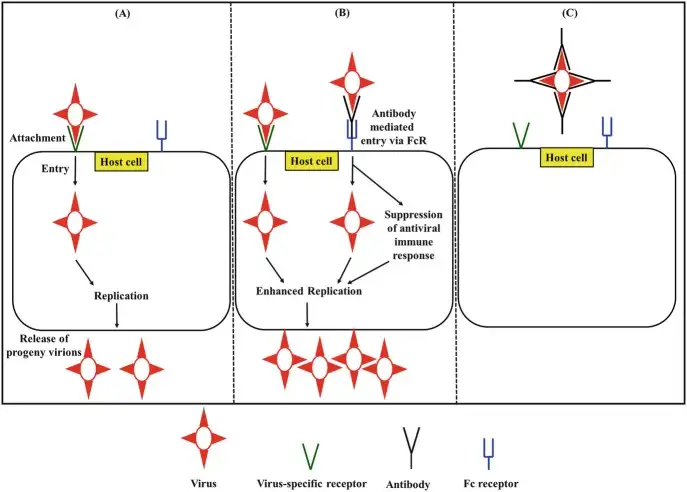

登革热最令人费解的特征,是二次感染往往比初次感染更加严重。这在传染病史上几乎是独一无二的——通常情况下,初次感染后产生的抗体会为人体提供持久的保护。但登革热不同,它发明了一种邪恶的"借力打力"策略。

当一个人首次感染某种血清型的登革热病毒时,免疫系统会产生针对该血清型的特异性抗体。这些抗体能够有效地中和病毒,防止其感染细胞。然而,当同一个人后来感染另一种血清型的登革热病毒时,情况就会发生戏剧性的变化。原先产生的抗体虽然也能结合新的病毒,但无法有效地中和它。更糟糕的是,这些"非中和性抗体"会形成病毒-抗体复合物,然后通过抗体的Fc段结合到单核细胞和巨噬细胞表面的Fcγ受体上。

这种现象被称为"抗体依赖性增强"(Antibody-Dependent Enhancement,ADE)。通过这条通路,病毒获得了进入原本不易感染的免疫细胞的"后门"。研究表明,ADE可以使病毒在感染细胞中的复制效率提高100倍以上。更令人震惊的是,最近的研究还发现,当病毒通过ADE途径进入细胞后,它会主动抑制细胞的抗病毒反应,这一过程被称为"内在性ADE"。

1960年代至1970年代,美国科学家Scott Halstead在泰国进行了一系列开创性的研究,首次提出了ADE的概念。他观察到,在曼谷的登革热患者中,出现严重出血热的病例大多是在二次感染的患者中。这一发现彻底改变了人们对登革热发病机制的理解。2017年,一项在尼加拉瓜进行的长达多年的儿童队列研究终于为ADE在人类中的作用提供了确凿的证据。研究发现,体内存在特定浓度抗体的儿童,患重症登革热的风险最高;而抗体浓度极低或极高的儿童,风险反而较低。这意味着,抗体对登革热的影响呈现出一个"倒U型"曲线——太少无法保护,太多能够中和,而处于中间浓度时则会增强感染。

2017年,菲律宾爆发的Dengvaxia疫苗争议,就是ADE最惨痛的现实案例。这款由赛诺菲公司研发的登革热疫苗,在接种前已经感染过登革热的个体中效果良好,但在从未感染过的个体中,却可能增加患重症登革热的风险。当这一风险被揭露时,菲律宾已经有超过80万名学童接种了疫苗,引发了大规模的恐慌和公共卫生危机。这一事件深刻地揭示了登革热疫苗研发的困境:如何设计一种能够同时保护四种血清型的疫苗,而不触发ADE?